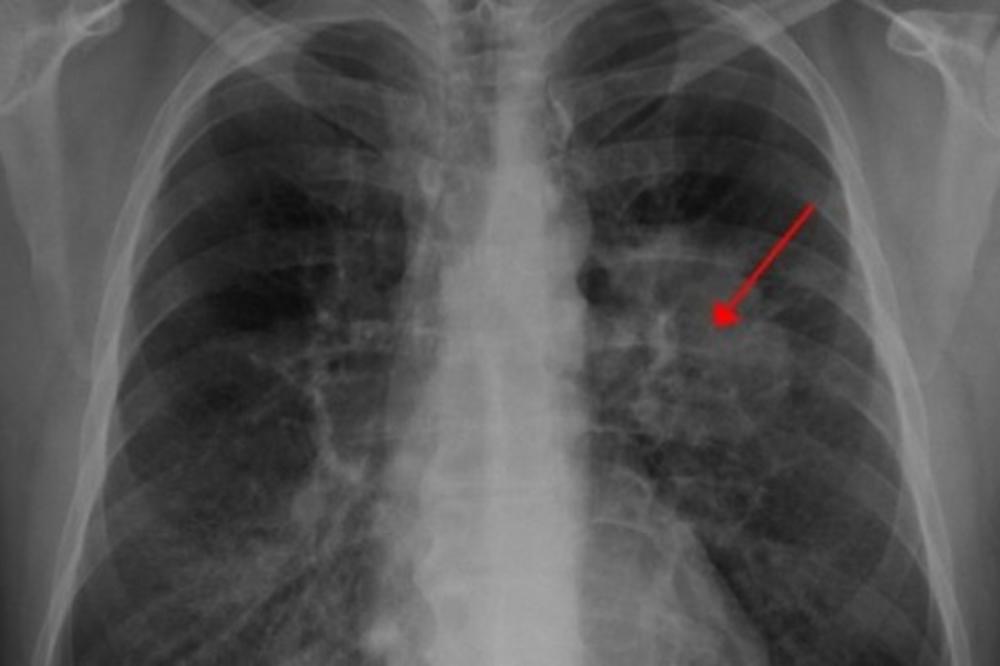

Rak pluća je fatalna bolest, ali ako se rano dijagnostikuje može ozbiljno da poveća šanse za izlečenje.

Kod ljudi sa karcinomom pluća simptomi se ne javljaju često dok stanje nije dostiglo kasniju fazu bolesti.